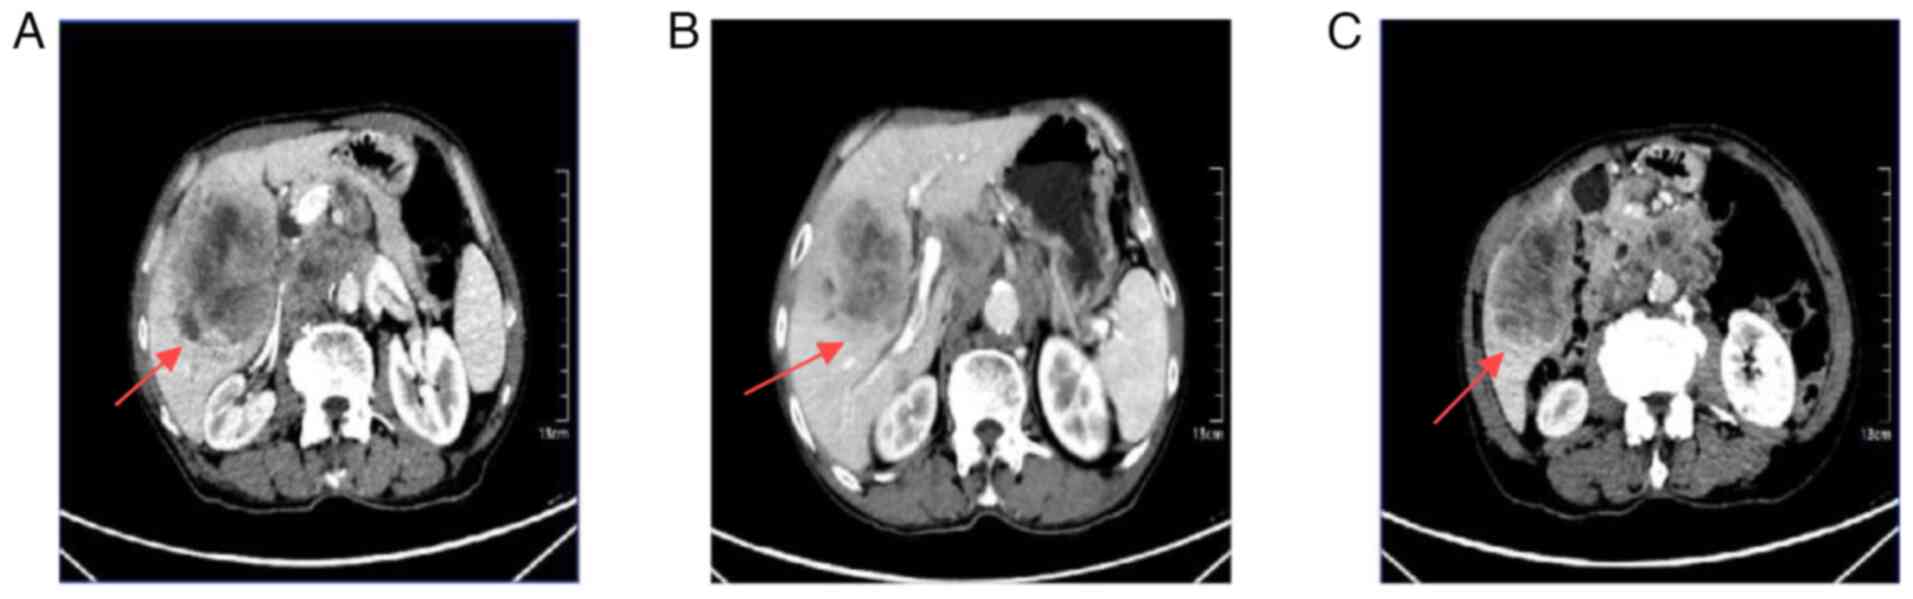

CT imaging showed multiple low-density nodules and masses beneath the capsule of the right hepatic lobe and within the right lobe of the liver, raising suspicion for potential hepatocellular carcinoma or intrahepatic cholangiocarcinoma with subperitoneal and intrahepatic multiple metastases (Fig. 1A). Thrombus formation was noted in the lumen of the right branch of the portal vein (Fig. 1B). The gallbladder was not clearly visualized. The kidneys showed multiple cysts. Multiple enlarged lymph nodes were identified in the posterior mediastinal paraspinal region, hepatic hilum and retroperitoneum, some of which were partially fused, suggestive of metastatic disease (Fig. 1C).

Figure 1.

Abdominal computed tomography images at the patient's initial consultation. (A) Multiple intrahepatic metastases (arrow). (B) Thrombus formation within the right branch of the portal vein (arrow). (C) Multiple enlarged lymph nodes in the retroperitoneal paraspinal region, hepatic hilum and retroperitoneum (arrow).